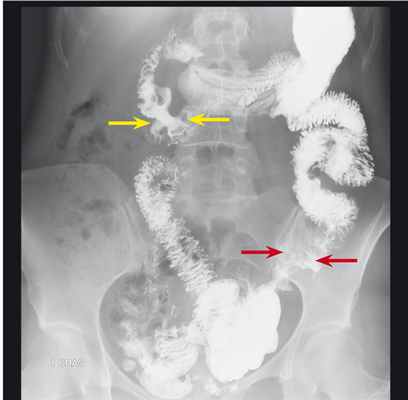

При проведении рентгенологического исследования пищевода, желудка и тонкой кишки были выявлены следующие изменения ( рис. 1 ): в нисходящем отделе двенадцатиперстной кишки с незначительным переходом на нижний горизонтальный отдел определялось стойкое неравномерное сужение просвета до 8 мм протяженностью до 45 мм без рельефа; на этом фоне визуализировались два округлых дефекта наполнения с четкими ровными контурами размерами 13 × 7 мм и 7 × 5 мм. На расстоянии 180 мм от связки Трейца — участок стойкого сужения по типу «яблочного огрызка» протяженностью 45 мм с уменьшением просвета до 3 мм, проксимальнее данного участка на протяжении 40 мм контуры кишки неровные, с множественными дефектами наполнения неправильной формы, перистальтика на данном участке не прослеживалась. В остальных отделах тонкой кишки ширина просвета обычная, складки слизистой не утолщены. Рентгенологическая картина была расценена как более соответствующая лимфоме тонкой кишки.

Рис. 1. Рентгенограмма тонкой кишки больной В., 44 лет. Фото авторов.

Примечание. Желтыми стрелками отмечен пораженный участок двенадцатиперстной кишки, красными стрелками — пораженный участок тощей кишки